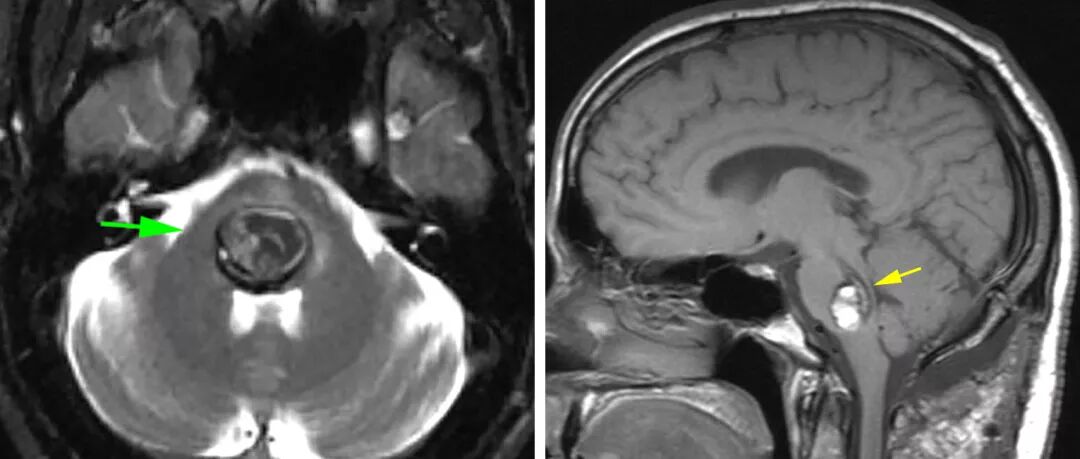

图2:对于手术计划,T1加权序列最适合于用“两点”法建立最短的经神经手术通路。第一点是病灶的中心,第二点是最接近软脑膜或室管膜表面的病灶边缘。这两点的连线直指病灶长轴,被认为几乎是到达病灶的最佳硬膜下通路。

图3:图示一个桥脑后部的CM,有一薄层完整的第四脑室底(左向箭号)。尽管最短的手术通路明显是沿第四脑室底进入,但最终选择经小脑中脚的外侧入路(右向箭号)。第四脑室底的薄层组织有重要功能,包含面丘。注意T1序列在检测神经组织方面优于T2序列,而T2序列容易被含铁血黄素引起的晕状伪影所干扰。

图12:这个桥脑延髓海绵状血管畸形主要位于脑干中央。病灶后缘有一薄层环状的正常第四脑室底,无法采用后正中入路(红色箭号)。笔者采用左侧乙状窦后入路(绿色箭号)在三叉神经与面/听神经之间切开软脑膜进入病灶的上段。此外,病灶在桥脑延髓交界水平已到达软脑膜表面,也经这个第二手术通路(蓝色箭号)切除病灶的下极。